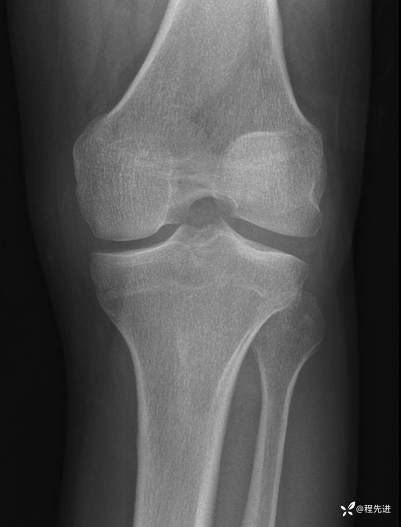

左膝关节正、侧、轴位DR:

img